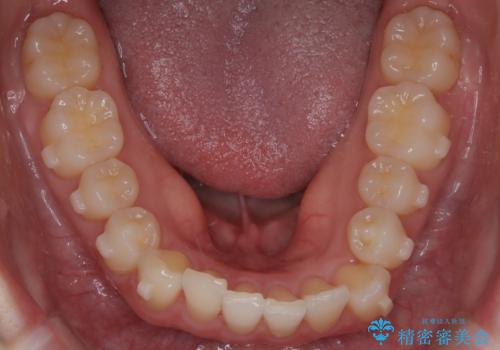

- 左上2の反対咬合(交叉咬合)をインビザラインを用いて治療しました。反対咬合は、歯列の不正咬合の一つであり、上の歯が下の歯よりも内側に位置する状態です。反対咬合は咀嚼や発音に影響を与えることがあります。

左上2の反対咬合をインビザラインで治療する際に、IPR(Interproximal Reduction)を行いました。 IPRとは、隣接する歯の間のエナメル質をわずかに削る手法で、歯の幅を減少させることによって歯列を整える技術です。